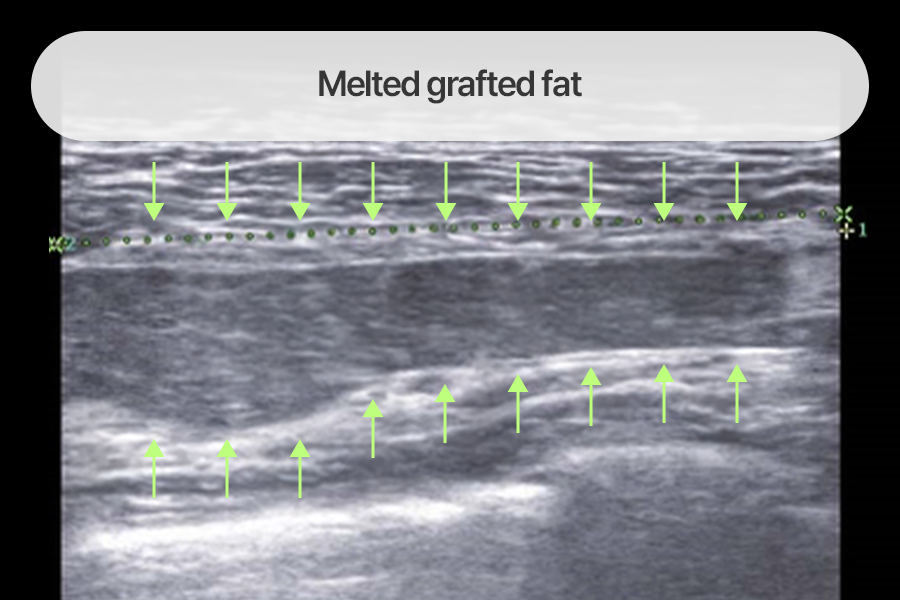

Case where melted fat formed a band across the breast

Non-engrafted fat necrosis masses formed a long band across the breast,

and a large amount of calcification was observed in endoscopic findings.

We removed various fat graft side effect lesions under the guidance

of imaging devices such as ultrasound and endoscopy.